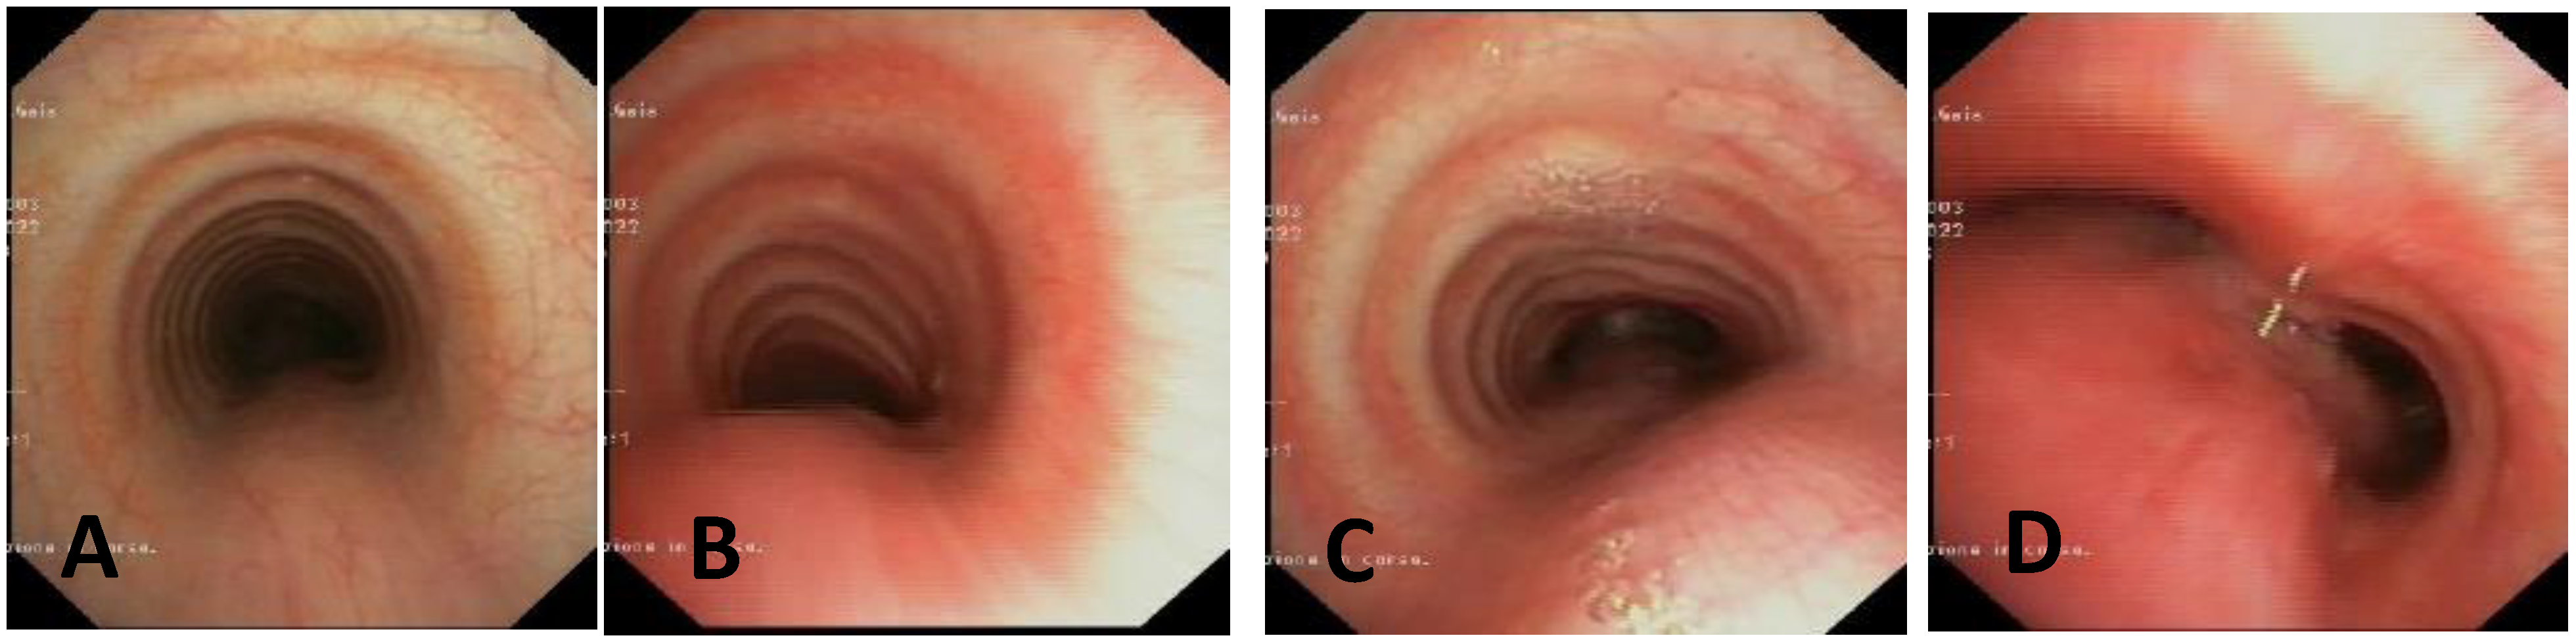

| Score: 0 | Pulsating extrinsic deformation on the anterior tracheal wall, reduction in the APD of the trachea of less than 50% compared to the suprastenotic tract, even during expiration. Good representation of the cartilaginous rings. Figure 9, score 0 |

| Score: 1 | Reduction in the tracheal APD between 50% and 75% compared to the suprastenotic tract, with an absence of contact between the anterior tracheal walls and the pars membranacea, even when the patient performs abdominal straining. Good representation of the cartilaginous rings. Figure 9, Score 1 |

| Score: 2 | Reduction in the APD of the trachea between 75% and 90% compared to the suprastenotic tract and/or anterior tracheal wall and pars membranacea, tending to touch, without complete closure of the lumen, even when the patient performs abdominal straining, with poor representation of the cartilaginous rings. Figure 1, score 2 |

| Score: 3 | Reduction in the APD of the trachea is already greater than 90% during the expiratory phase, when the tracheal lumen completely closes. Figure 9, score 3 |